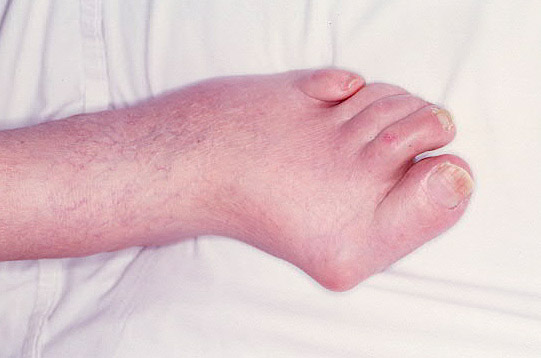

Bursitis primer metatarsiano